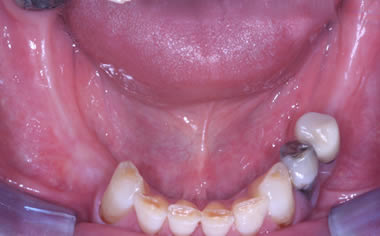

More back teeth replaced by dental implants

Case Four (4 images)